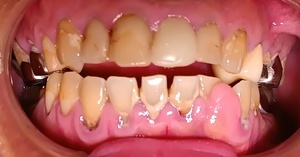

Before(歯石除去前)

下の前歯裏側にびっしりと付着した茶褐色の歯石が、歯間まで覆っています。表面が粗く、不衛生な印象を与えています。